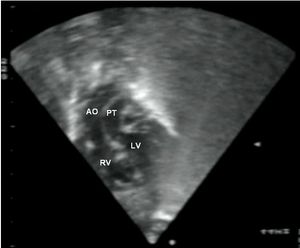

심장 초음파 검사는 심장의 구조와 기능을 정확하게 평가하는 초음파 검사이며, TGA의 특징을 보여줄 수 있다. 이 검사를 통해 TGA를 확진할 수 있다.[3]

평생 심장 전문의의 추적 관찰이 필요하다. 수술을 받은 대부분의 영아는 증상이 완화되고 정상적인 생활을 할 수 있다. 발생할 수 있는 잠재적인 합병증으로는 관상 동맥 문제, 심장 판막 문제 또는 불규칙한 심장 박동(부정맥) 등이 있다.[2]8. 추가 이미지

약어: LV 및 RV=좌심실 및 우심실, PT=폐동맥, VSD=심실 중격 결손, PS=폐동맥 협착.]]